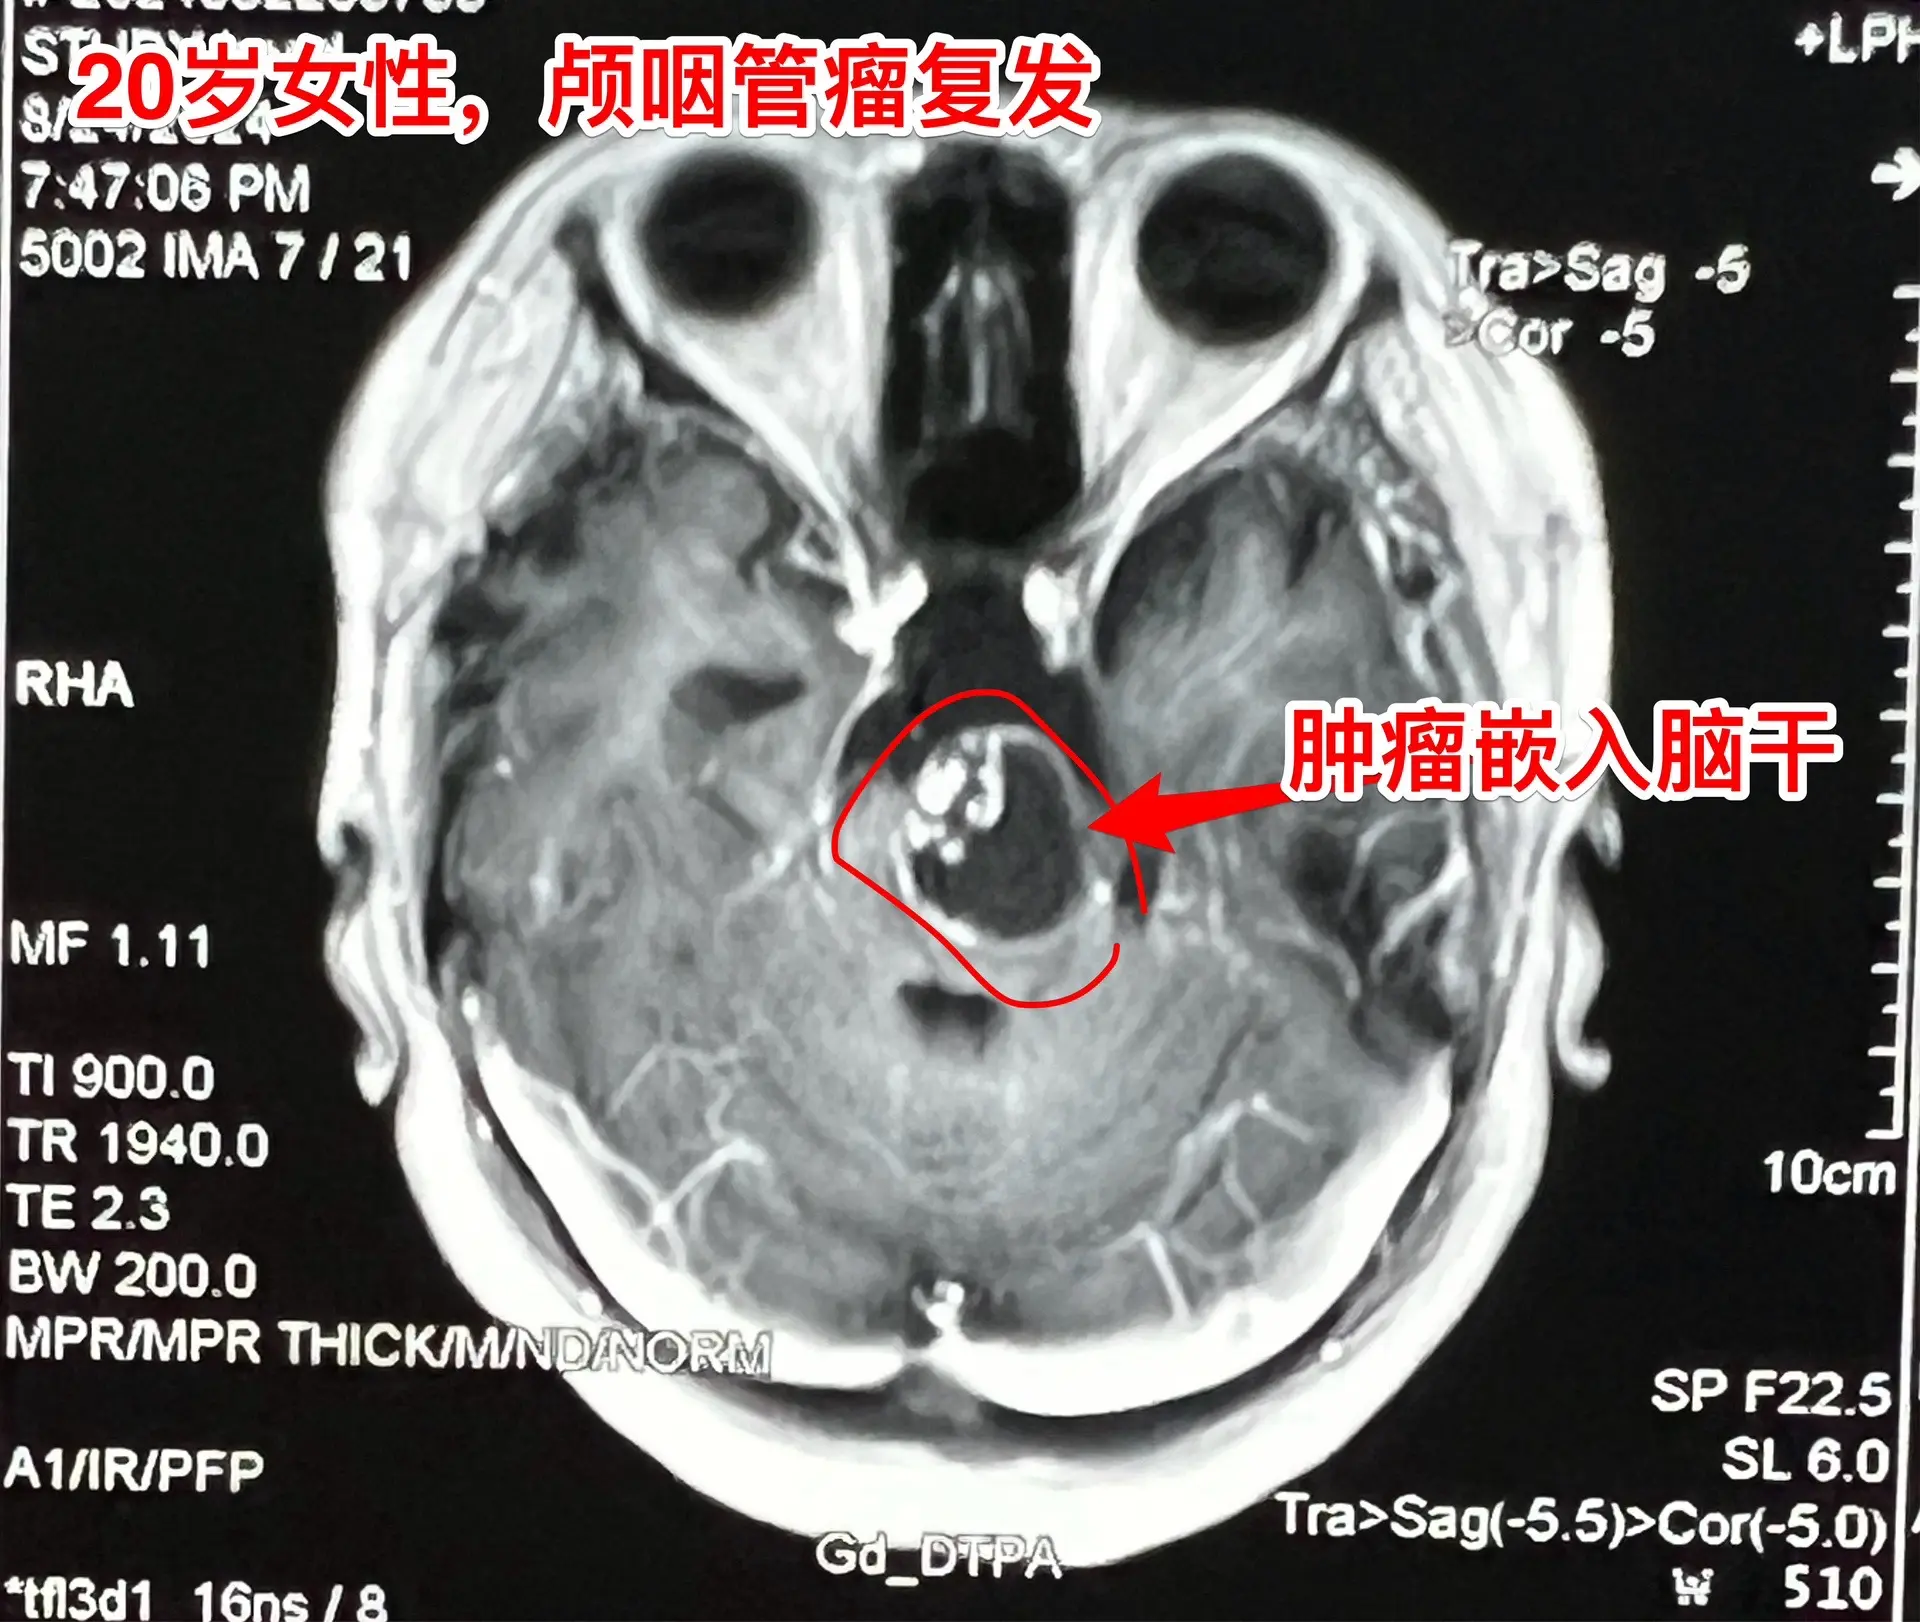

颅咽管瘤第七次开颅手术,恢复顺利。20岁女性,广东省东莞人。不幸的孩子,患颅咽管瘤,10年时间内第七次作手术。 第一次、第二次手术在广州市某医院作的。从2016年开始在我科先后作了四次手术。 三个月前患者出现贫血、头晕,在广东省查胃镜,发现食道静脉曲张、出血,有严重的贫血,还怀疑肝脏硬化。 今年八月患者出现左侧面部麻木、右侧上下肢活动力弱,8.24磁共振显示肿瘤复发,而且肿瘤嵌入脑干内。8.30患者来到三博脑科医院住院,还能自己行走。住院后症状进展很快,不能独立行走。 9月6日为她作了手术。这是第七次开颅手术。手术中将肿瘤完全切除。 虽然患者体质很弱,令人惊奇的是,术后她居然恢复很顺利,精神状态好,右侧上下肢无力症状明显改善,一天比一天好,现在能独立行走。很快就能出院了。但愿肿瘤不再复发了!